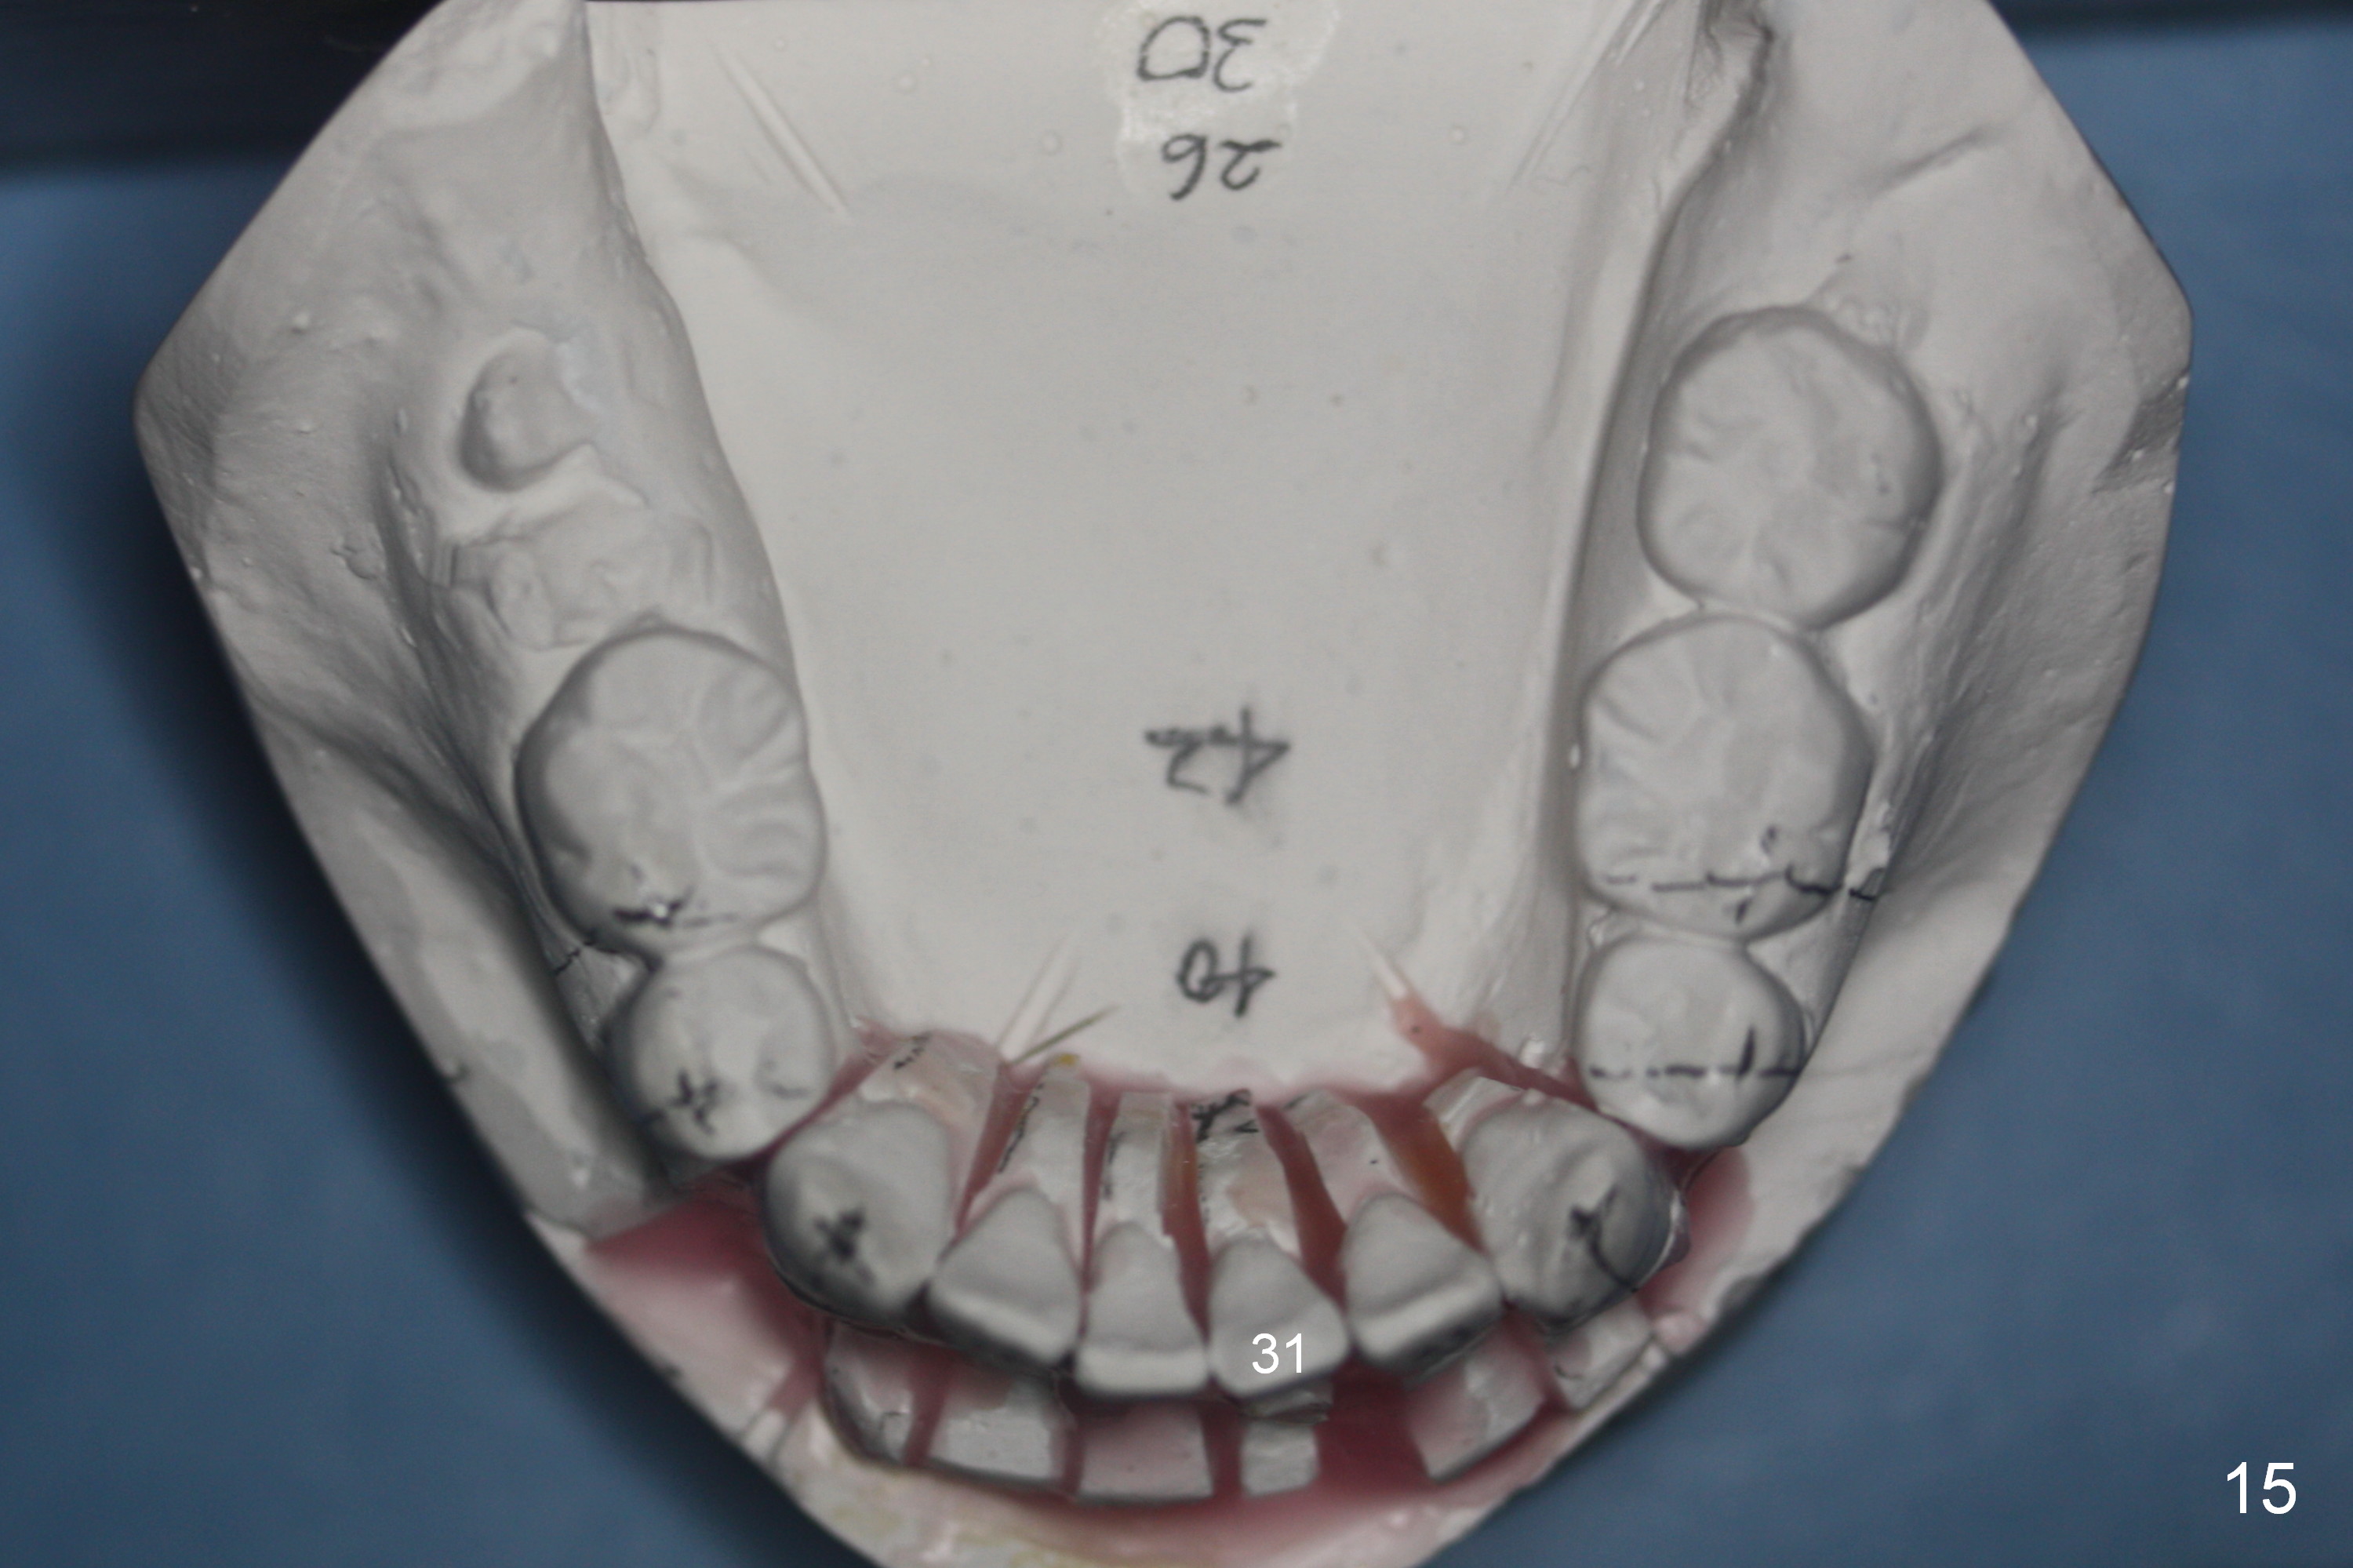

A 37-year-old man requests orthodontic treatment for severe crowding with 3 blocked-out incisors (Fig.1-5: 12,22,31 (International numbering, pronounced one two, two two and three one)). The upper and lower arches are pointed (Fig.4,5). The best option is extraction of 4 bicuspids (Fig.11-15).

His profile is convex with lip strain. After alignment of the anterior teeth, check the facial profile to determine whether it is necessary to distalize the anterior teeth or not. If it is, the distalization will be done with the aid of an implant at 47 (Fig.1,5 (residual roots)) and 3 mini-implants at the 3 other quadrants. An extra mini-implant will be placed at the upper right quadrant to intrude 17 (Fig.1 arrow).

There may be limited space for placement of these blocked out incisors. Do not have to place them at the time of bracketing until space has been created by arch wire sequence and open coil spring. It would be ideal to use labial torque brackets or place brackets upside down (Jenny's idea). In fact, the patient finishes ortho treatment in an orthodontist's office without intrusion of 17. Magicore will be placed at 47 to intrude 17 or simply for restoration.